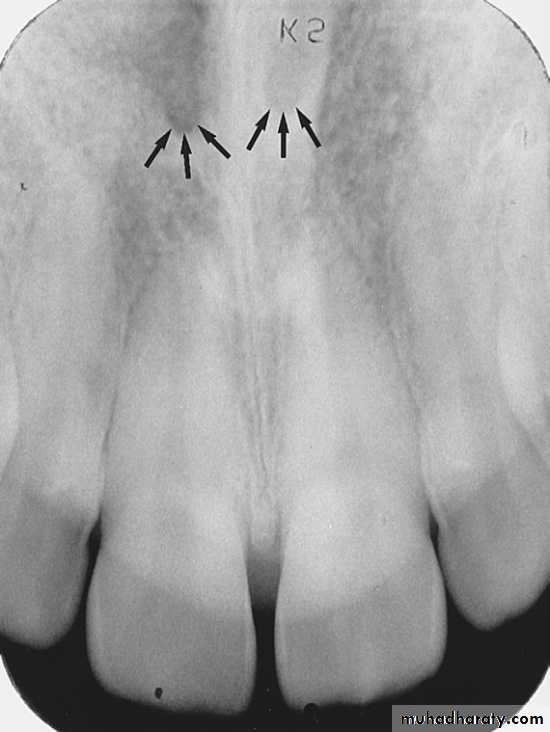

INCISIVE FORAMEN: The incisive foramen is an opening in the bone that is located at the midline of the anterior portion of hard palate. Radiographically the incisive foramen appears as a small ovoid or round radiolucent area located between root of maxillary central incisor.

Superior Foramina of Incisive Canal

The superior foramina of the incisive canal are two tiny openings or holes in bone that are located on the floor of the nasal cavity. The superior foramina are the openings of two small canals that extend downward and medially from the floor of the nasal cavity. These two small canals join together to form the incisive canal and share a common exit, the incisive foramen.Appearance. On a maxillary periapical image, the superior foramina appear as two small, round radiolucencies located superior to the apices of the maxillary central incisors

MEDIAN PALATEL SUTURE: The median palatal suture is the immovable joint between two palatine process of maxilla. Radiographically the suture appears as thin radiolucent line between the central incisor, the median palatal suture bounded in both side by dense cortical bone that appear radiopaque.